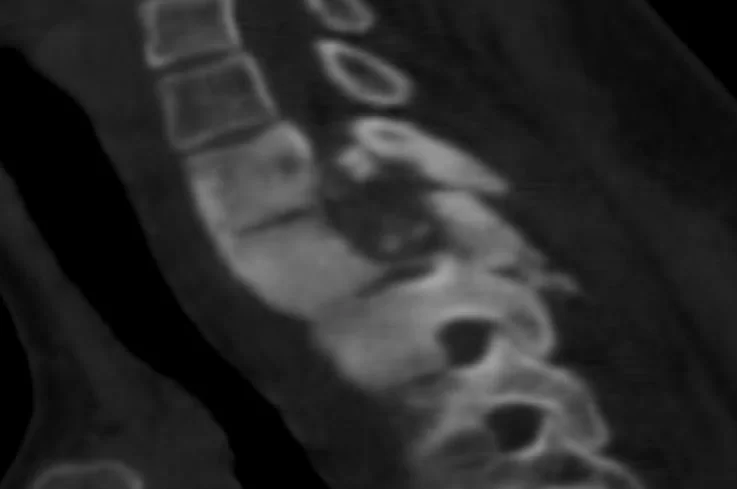

Ο απεικονιστικός έλεγχος έλεγχος με μαγνητική και αξονική τομογραφία της αυχενικής μοίρας της σπονδυλικής στήλης ανέδειξε χωροκατακτητική εξεργασία στο ύψος του Θ1-Θ2 σπονδύλου

Προεγχειρητικός Απεικονιστικός Έλεγχος (οβελιαίες εικόνες)